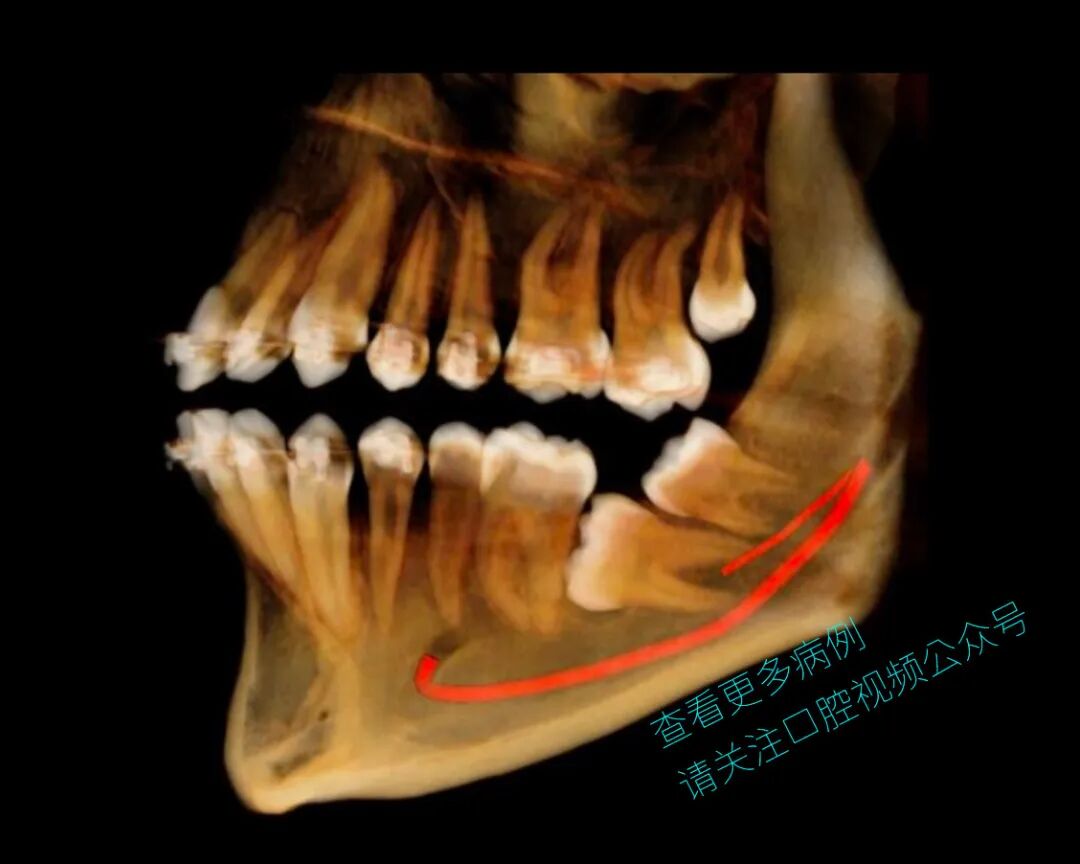

患者为18岁男性,既往接受过正畸治疗。37号牙水平阻生,紧贴36号牙。

手术拔除了38号牙,并在下颌升支植入一枚2×14 mm微型种植体,用于牵引并使37号牙平行移动。